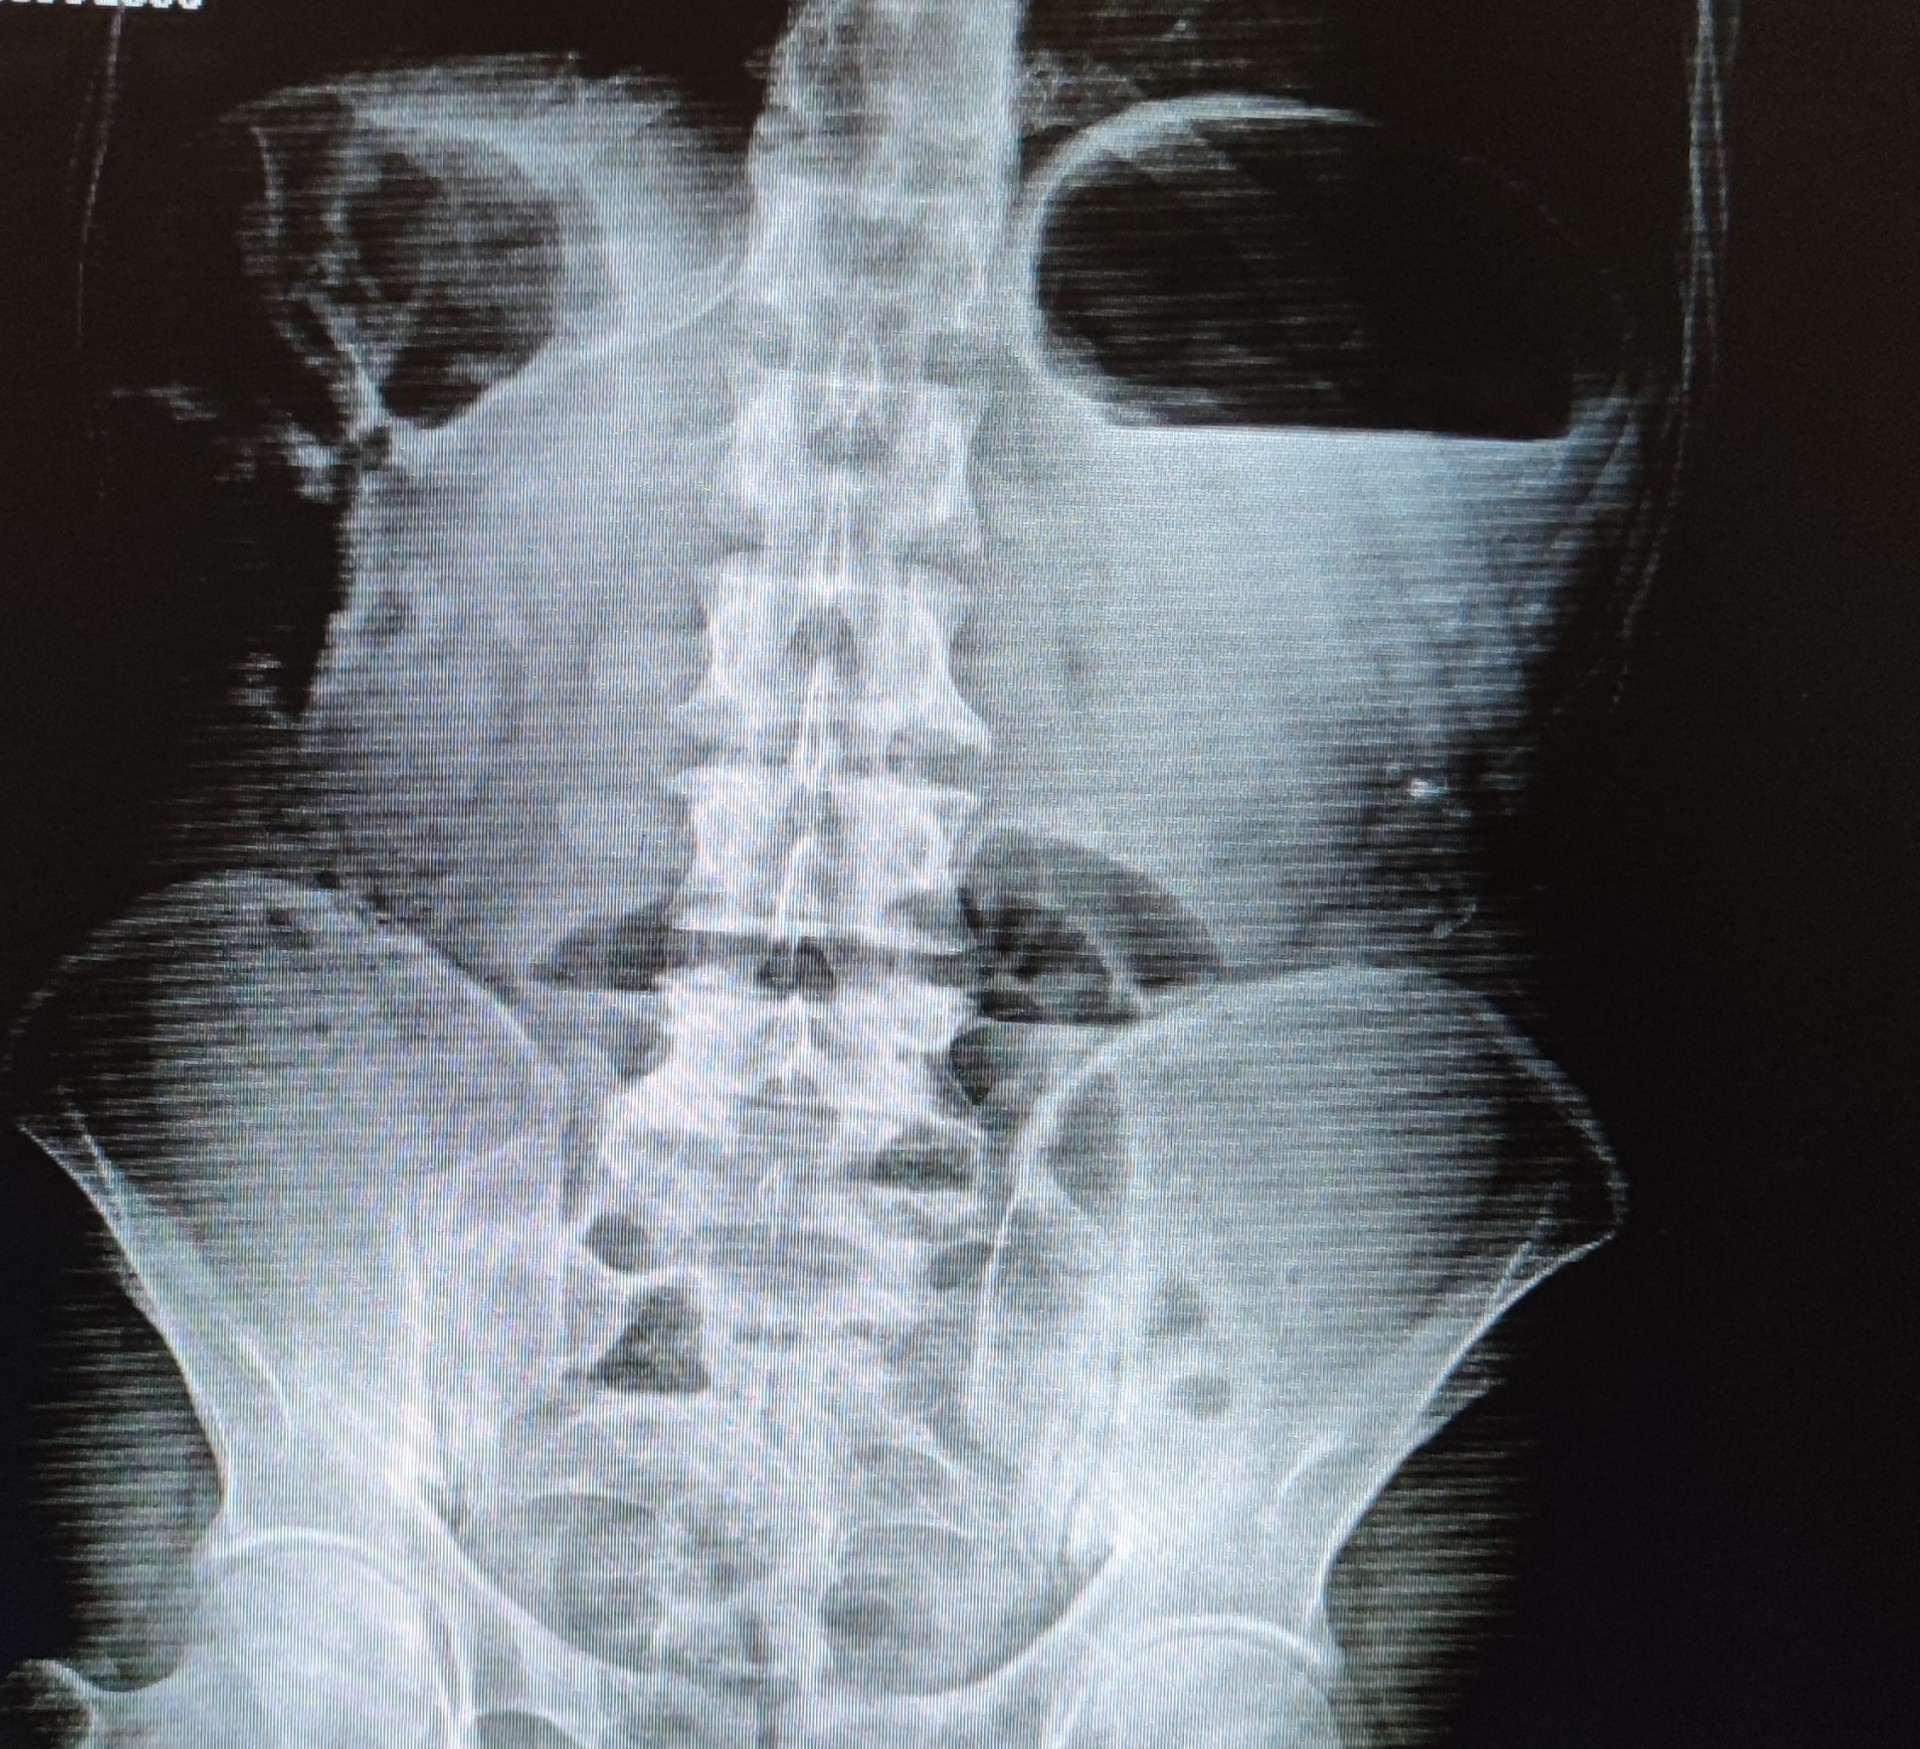

bağırsak hareketlerinin bozularak kişinin gaz ve gaita çıkaramaması sonucu gelişen durumdur.tıkayıcı bir kitle sebep olabileceği gibi nörolojik veya geçirilmiş cerrahilere bağlı da olabilir. ayakta direkt batın grafisi çekildiğinde hava-sıvı seviyelenmeleri dediğimiz şu görüntü gözlenir ve hastanın yeme içmeyi kesip cerrahi hazırlığına alınması gerekir.